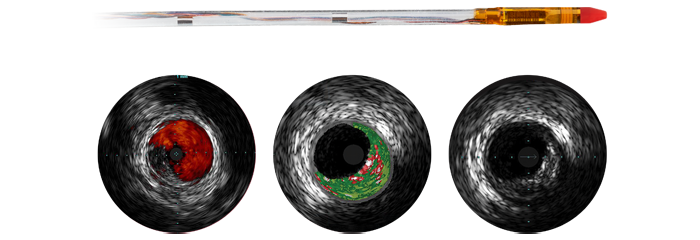

Eagle Eye Platinum

Digital IVUS catheter

The Eagle Eye Platinum digital IVUS catheter is the #1 choice of physicians for intravascular imaging (in the US). *As a unique plug-and-play intravascular imaging catheter it is designed for ease of use and deliverability. Features include a soft tapered tip, GlyDx hydrophilic coating for increased lubricity, a long, rapid exchange lumen for improved pushability, three radiopaque markers, and compatibility with IntraSight and SyncVision for co-registration with angiography.